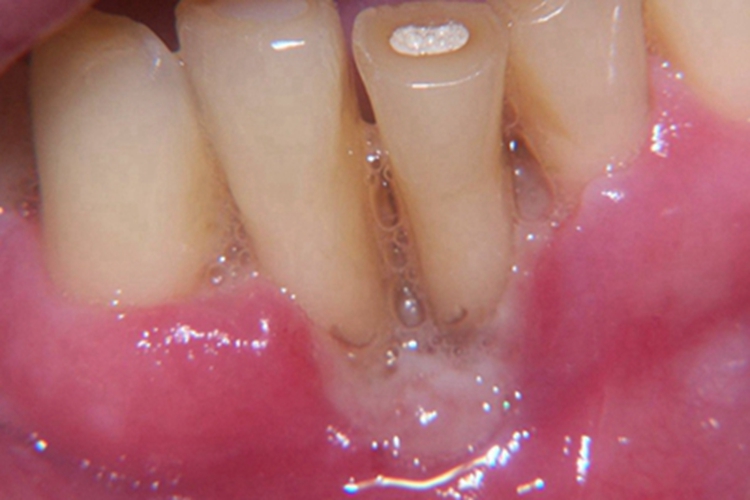

牙龈炎的症状可以表现为局部溃疡,表面颜色泛白,向内凹陷,患者可有疼痛等不适症状,损害可自行消退,部分患者可持续轻度炎症数年。

牙龈炎常见的病因是口腔卫生差,不良的口腔卫生使牙菌斑沉积于牙齿与牙龈之间,造成龈沟加深,另外牙结石、不良修复体等也可造成牙龈炎的发生。